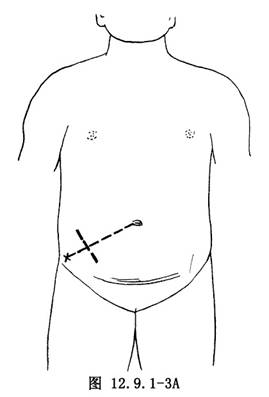

⑴右下腹斜切口(mc burney):右下腹斜切口,即麥克伯尼(Mc Burney’s)切口。經臍孔與右髂前上棘連線外中1/3交點(麥克伯尼點)做與該連線垂直的皮膚切口(圖12.9.1-2,12.9.1-3A)。此切口肌肉交叉,癒合較牢固,不易形成切口疝;且距闌尾較近,便於尋找。切口一般長5~7cm。對診斷有把握的病人多采用此切口。